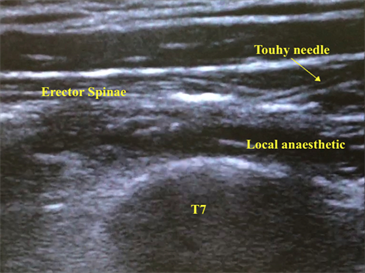

A 56-year-old gentleman (168 cm, 62 kg) underwent elective laparoscopic wedge resection of liver segment 6/7 and segment 8 for hepatocellular carcinoma. He was a hepatitis C carrier with Child’s A liver cirrhosis and was on antiviral therapy. An ESP block was offered as part of a multimodal analgesia approach and as an alternative to central neuraxial blockade. A single bolus ESP block was performed on the left T7 level with an 18 g Touhy needle. 20 mls of 0.4% Ropivacaine was injected into the plane under ultrasound guidance (Figure 1). Another ESP block was performed on the right T7 level with 20 mls of 0.4% Ropivacaine followed by catheter insertion which was anchored at 10 cm with 5 cm in space.

Figure 1. Real-time ultrasound image of the erector spinae plane block with 18 g Touhy needle in situ. The deposition of local anaesthetic can be seen in the plane between the T7 transverse process and the erector spinae muscle.